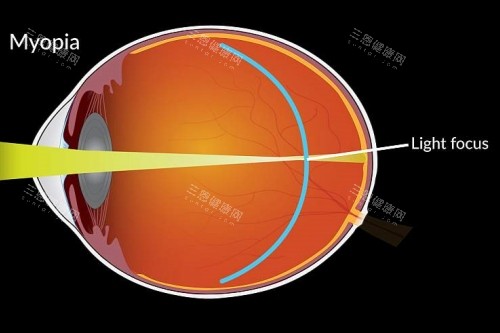

长期受近视困扰的鸡西市民而言,“鸡西做近视手术去哪做比较好”不仅是搜索关键词,更是关乎生活质量的重大决策。

眼镜压鼻梁、隐形眼镜引发干眼症、运动时频繁扶镜框……这些痛点让越来越多人将目光投向近视手术。

但面对全激光、晶体植入等术式选择,如何找到技术扎实、经验充足且服务规范的医疗机构?